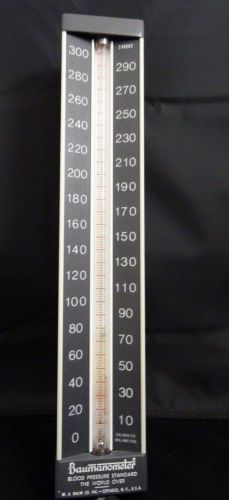

Baumanometer Wall Mount Mercury Blood Pressure

Welch Allyn CE0050 Sphygmomanometer with Durable Blood Pressure Cuff

7 x gauge lot sphygmomanometer pressure blood gauges Tycos Grafco Marshall +